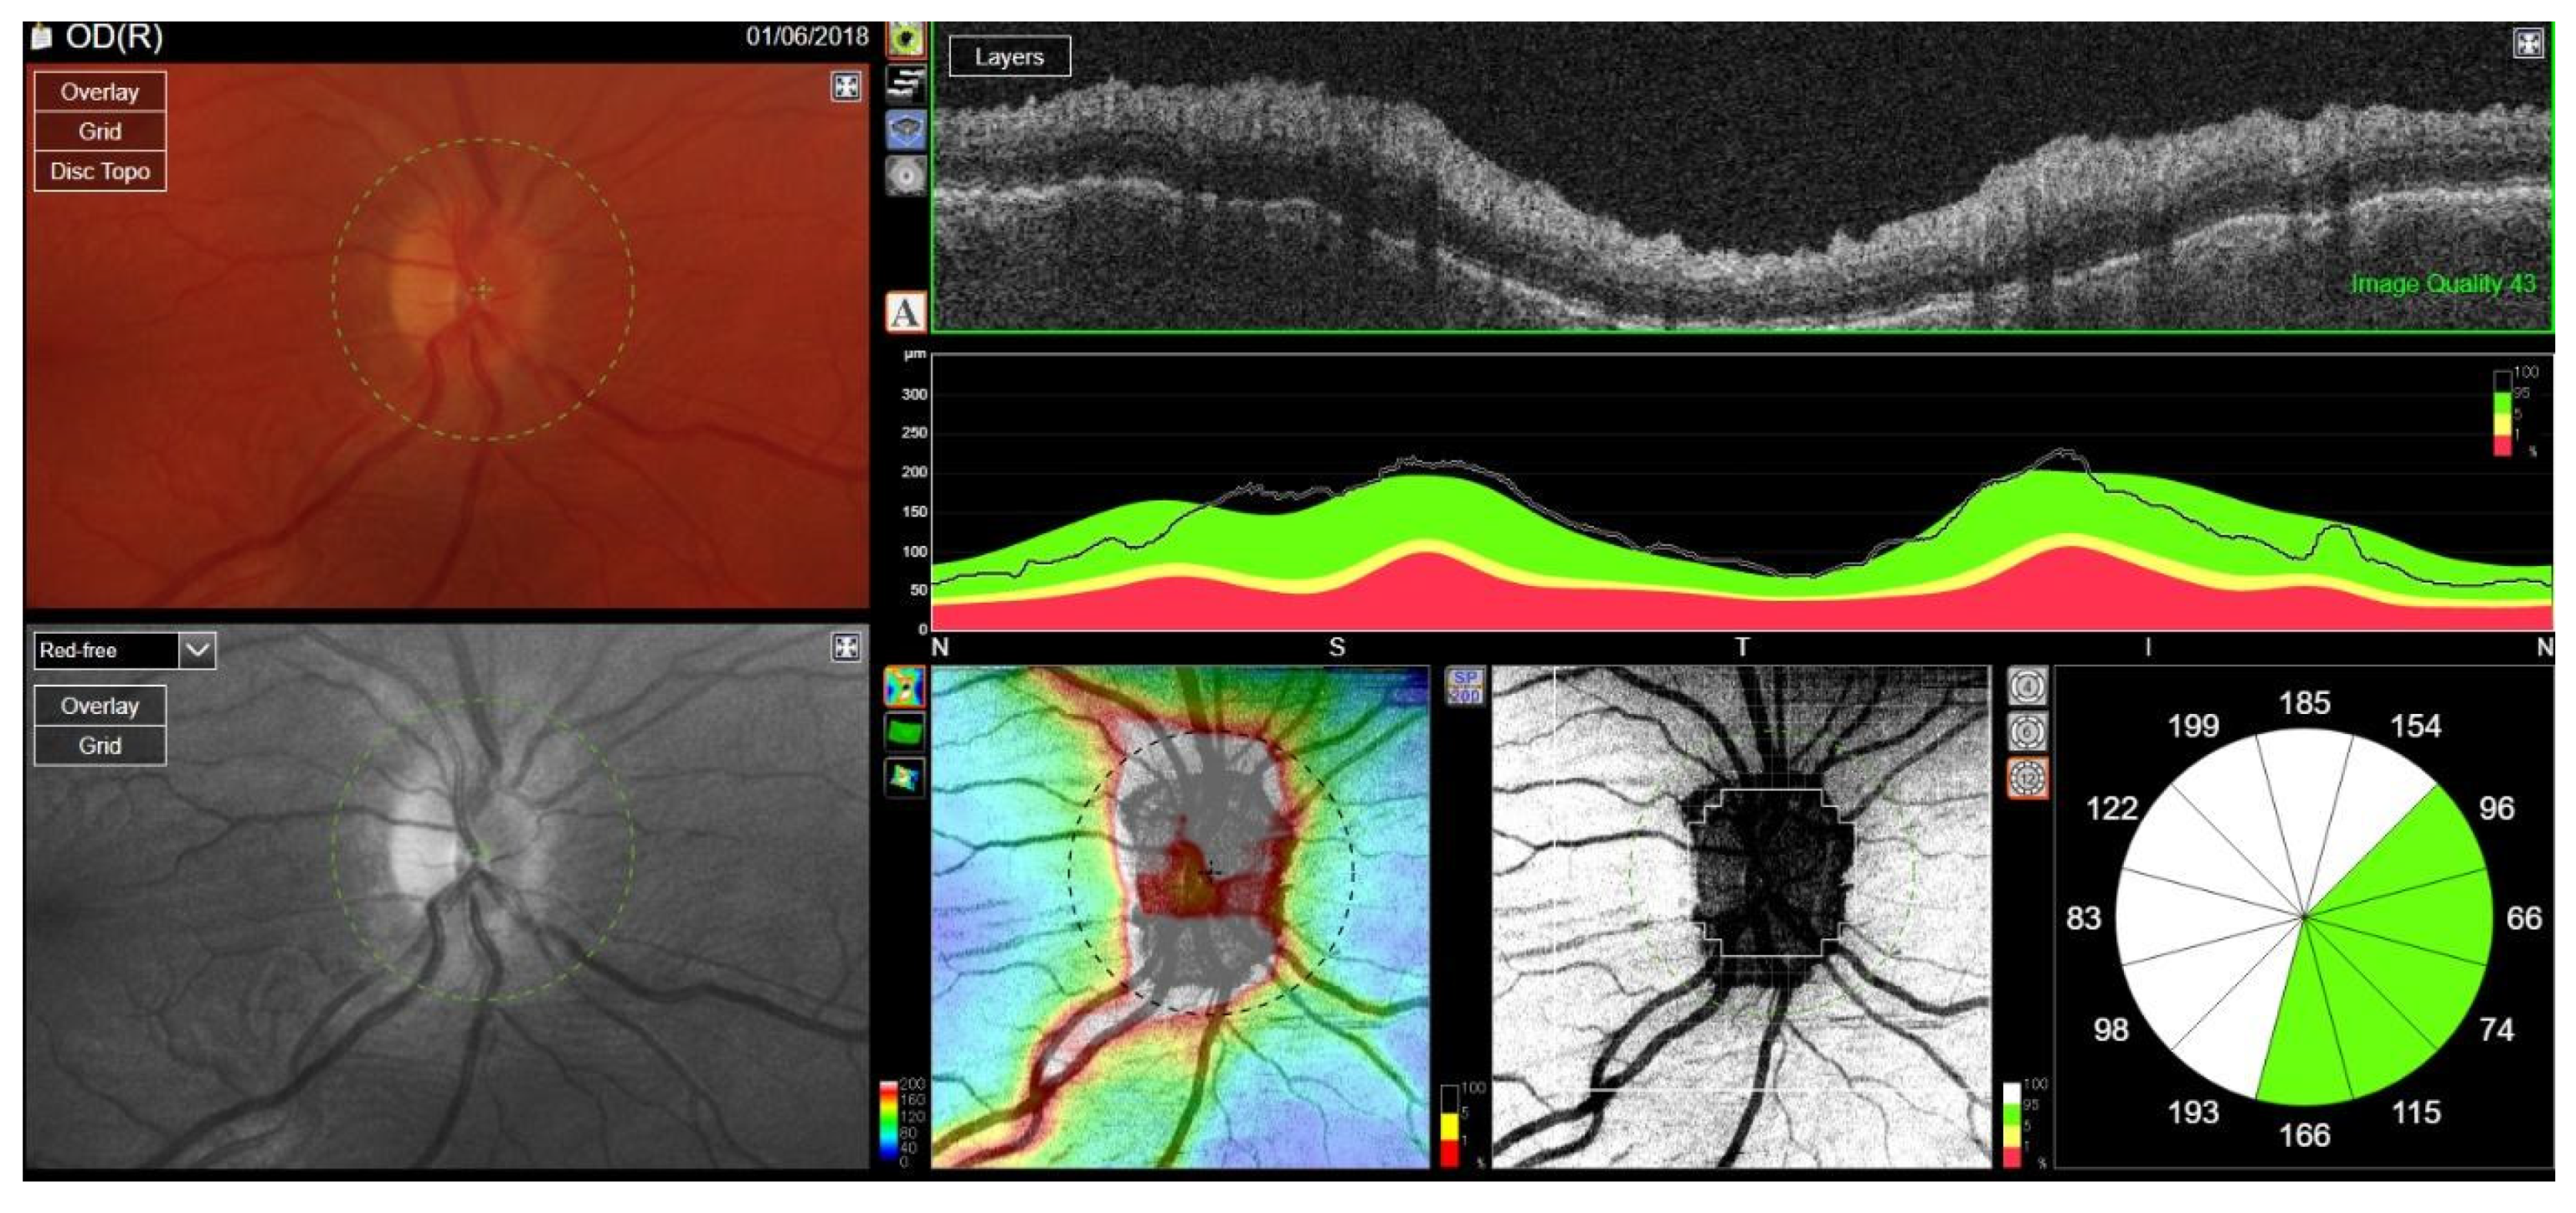

A month later, during an examination in the Ophthalmology Department, a CT scan revealed the modeling of the intraorbital structures on the right side by inflammatory granulation tissue, resulting in proptosis. Additionally, limited eyeball mobility in all directions, swelling and redness of the eyelids, conjunctival chemosis, secondary ocular hypertension (20.0 mmHg), and compressive optic neuropathy were observed.

BCVA in the RE decreased to logMAR 0.5, and disc edema was found on an ophthalmoscopic examination, confirmed in spectral-domain optical coherence tomography (OCT) of the optic nerve scans, illustrating an increase in the retinal nerve fiber layer (RNFL) thickness in the superior quadrant of the RE and scotoma in the lower sector of standard automated perimetry (Figure 21). The patient was qualified for urgent intravenous methylprednisolone (total dose: 2.625 g) and intravenous two-week administration of CYC (total dose: 1.2 g) with continuous oral prednisone therapy at a dose of 80 mg daily. Due to the lack of clinical response to CYC, treatment with RTX was initiated at a dose of 375 mg/m2/week for 4 weeks. The patient presented a good clinical response, with a complete resolution of the lesion confirmed radiologically 4 months after starting RTX.

Figure 21. OCT RNFL. Optic disc edema in the right eye caused by retrobulbar granulomatosis.